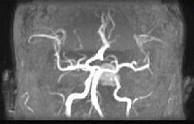

问题 男性,55岁,头痛一年余,两个小时前突然出现剧烈头痛,MRI检查如图所示,最可能的诊断为 ( )

选项 A、垂体瘤并卒中 B、动脉瘤 C、脑膜瘤 D、颅咽管瘤 E、垂体瘤

答案 A